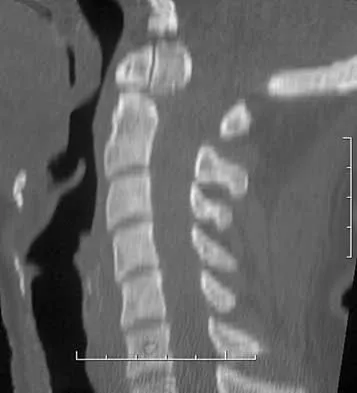

A 60-year-old man is evaluated in the ICU after a rollover motor vehicle accident 3 days ago. He has multiple upper and lower extremity trauma and was found unresponsive at the accident scene. Surgery is planned for the extremity trauma once the patient is medically stable. He remains intubated and the cervical spine is immobilized in a semi-rigid collar. Examination reveals mild erythema in the posterior occipital cervical region. Initial AP and lateral radiographs of the cervical spine have not revealed any obvious fracture. What is the most appropriate treatment option at this time?